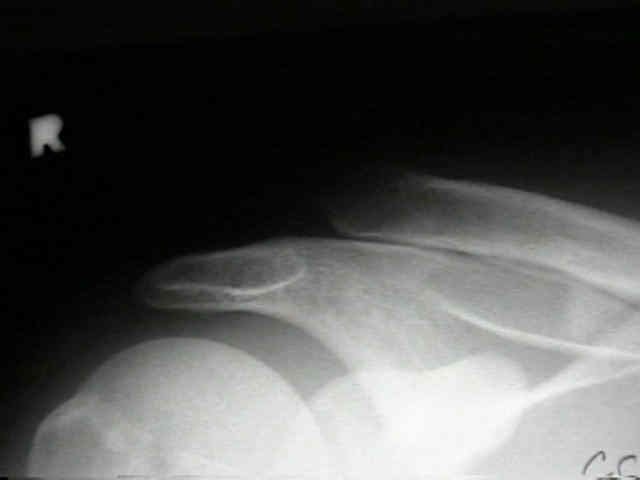

AC Joint 1 AC Joint 2 AC Joint 3 AC Joint 4

• 20-year-old who fell on tip of right shoulder, but did not show radiographic signs of AC joint injury in the ER;

• one month later the patient continued to have pain, and radiographs demonstrated greater than 100 percent displacement of AC joint on both AP and Cross Body AP (Cross Adduction View);